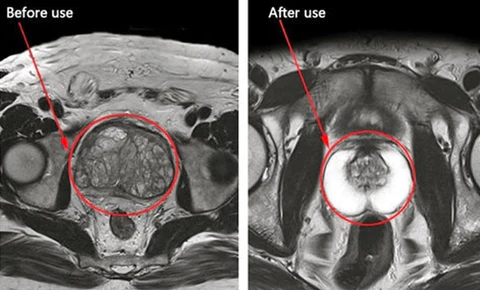

Hluboké účinky: před a po použití prstence prostaty

vpřed:

- Časté noční výlety na toaletu ovlivňují spánek.

- Přetrvávající nepohodlí v pánevní oblasti.

zadní:

- Frekvence močení v noci je výrazně snížena.

- Zmírňuje pánevní nepohodlí pro lepší každodenní pohodlí a mobilitu.